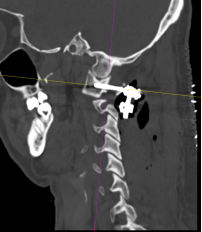

患者杨先生在春节后返苏的高速上不慎发生车祸,事故发生后患者感觉颈部剧烈疼痛,无法活动。当天送至我院后,在急诊拍摄颈椎CT显示:第一颈椎骨折,移位明显。

在仔细研究了患者的片子后,发现寰椎前后弓四处骨折,双侧侧块漂浮,寰齿间隙增大,后弓的骨折块还陷入到椎管内。尽管没有造成颈髓损伤,但稍有移动就可能导致瘫痪甚至死亡,因此姜主任确定该患者的最佳治疗方案为寰枢椎内固定手术。

该患者的治疗关键在于两个方面:一是能否将螺钉置入漂浮的寰椎侧块中从而达到骨折的复位及固定?二是该患者同时还伴有双侧枢椎椎弓根先天性发育不良、椎动脉高跨,能否顺利植入椎弓根螺钉?经过为期一周的颅骨牵引和术前准备,杨先生于近日接受了手术。对于此类颈椎手术,经验丰富的姜为民主任早已开展了多年,与以往不同的是这次手术多了一台“GPS”---“O”-臂机,这也是我院首次术中开机实用。